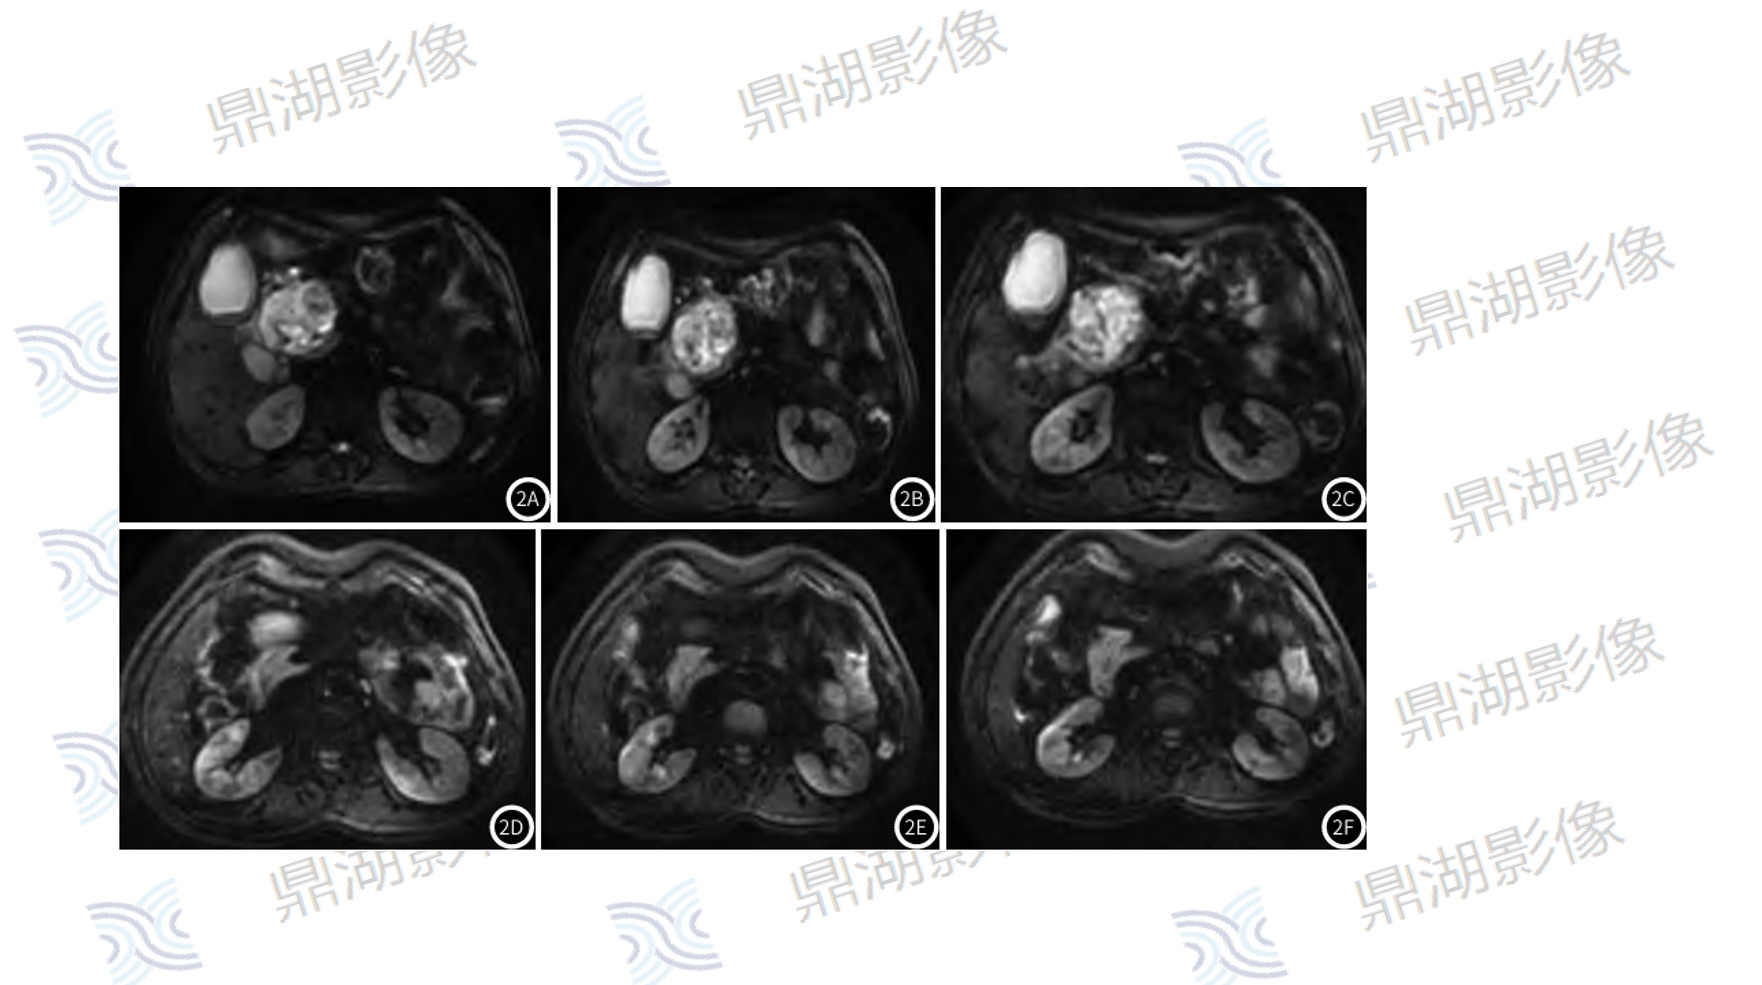

影像表现:胰腺钩突不规则软组织肿块,FDG摄取增高,SUVmax=4.3,病灶与邻近肠系膜上静脉分界不清,胰腺体尾部萎缩伴胰管扩张,胆总管及肝内胆管轻度扩张。